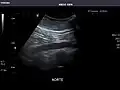

Spleen -

Spleen: Normal in size.